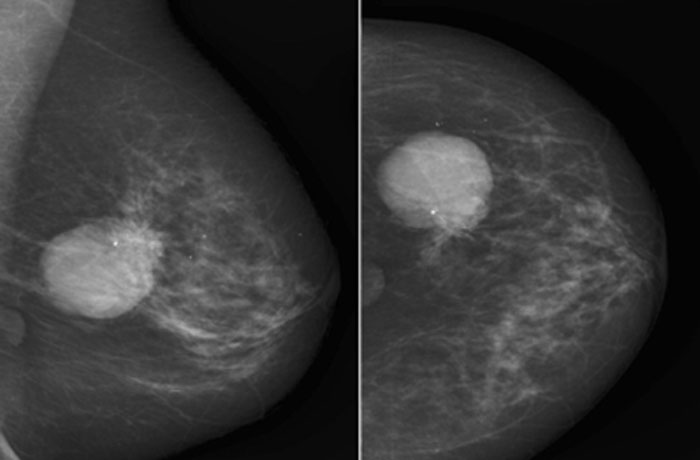

- УЗИ молочных желез и/или маммография;

Иногда целесообразно выбрать выжидательную тактику, например, в пубертатном периоде, менопаузе. Для образований менее 1 см выполняется тонкоигольная биопсия или трепанбиопсия. Динамическое наблюдение предусматривает прохождение маммографии раз в год и УЗИ дважды в год, важно также 1-2 раза в год посещать врача-маммолога.